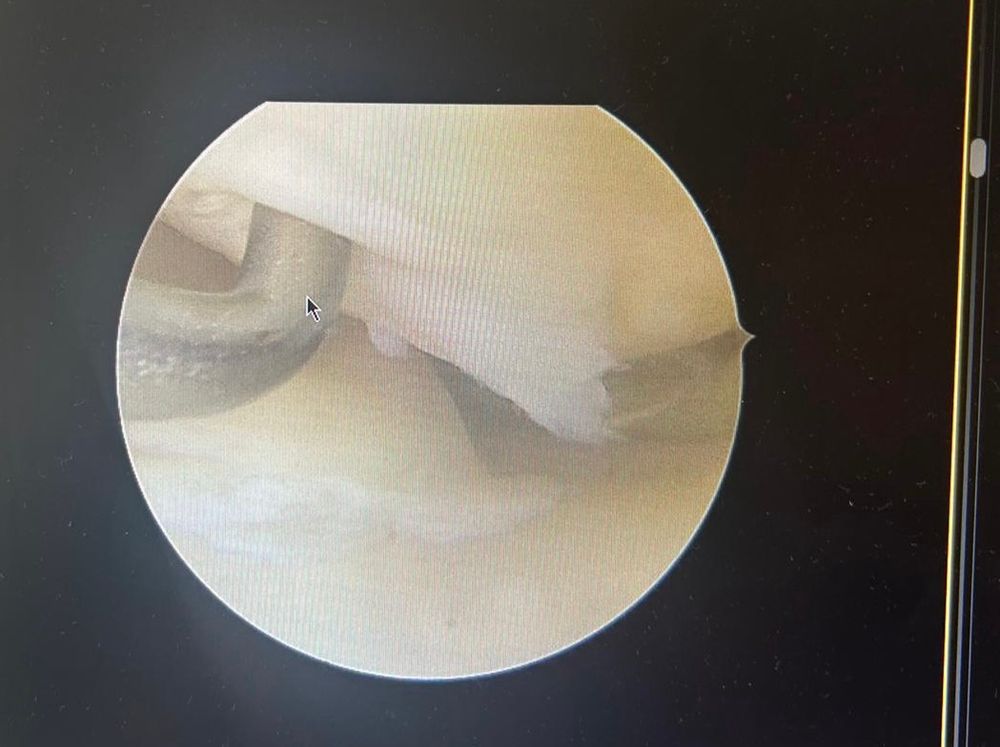

Hier ein Beispiel für einen eingeschlagenen Meniskus Riss , der sich immer in den Gelenkbereich innen eingeschlappert hat . Ein Befund der einen Minimal-invasiven Eingriff rechtfertigt.